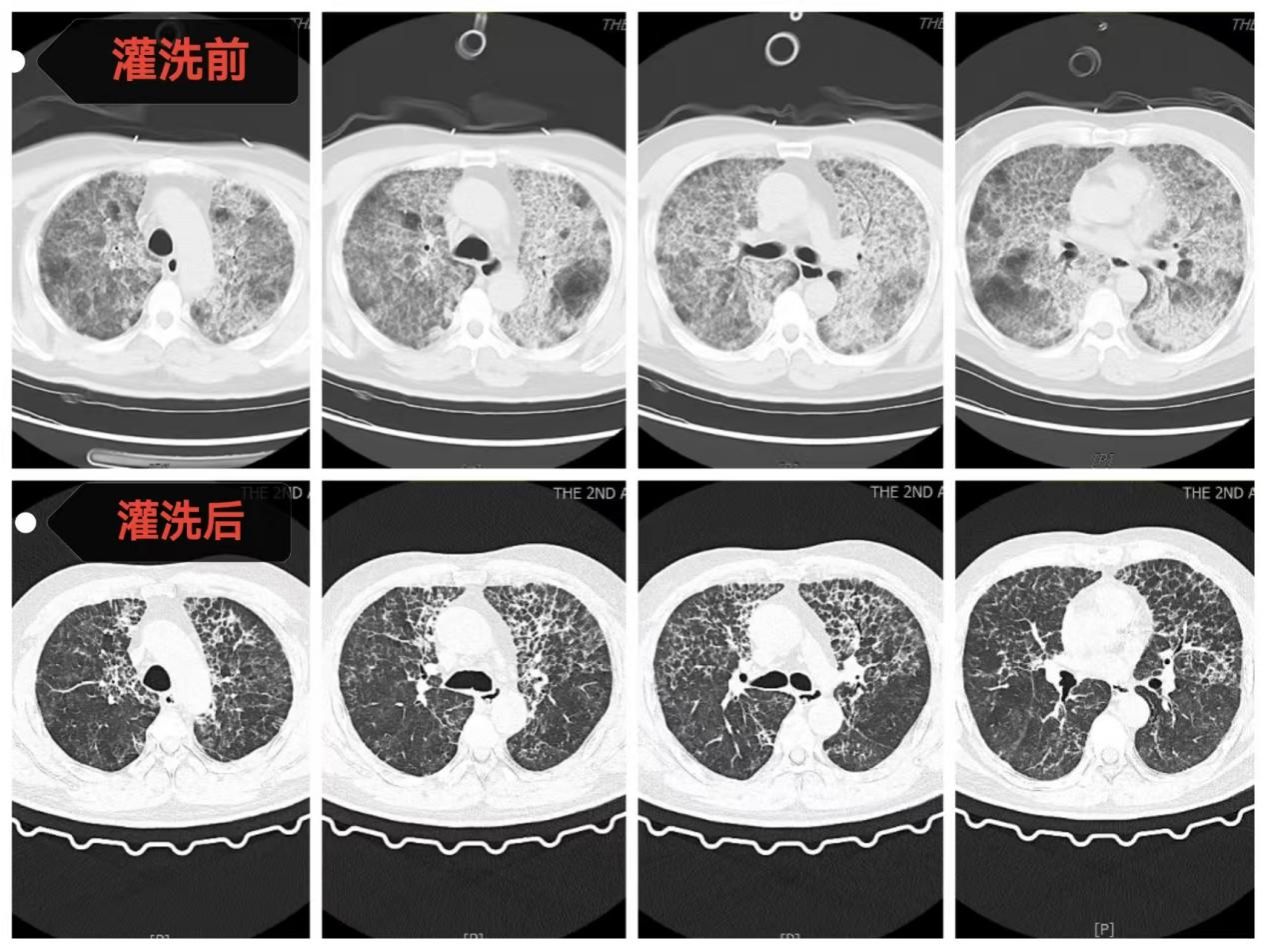

全肺灌洗前后影像资料对比

术后,患者在ECMO支持下转入呼吸与危重症医学科RICU继续治疗。在长达11天的ECMO支持期间,RICU医护团队日夜坚守,严密监测,精准调整抗感染、抗凝策略和ECMO、呼吸机支持参数。随着患者自身肺功能逐渐改善,复查血气指标显著好转,胸部CT显示双肺弥漫性阴影较入院时明显吸收。最终成功撤除ECMO,并顺利脱离呼吸机、拔除气管插管。出院时,患者在不吸氧的情况下,血氧饱和度维持在正常水平,活动能力恢复,实现了从“命悬一线”到“行动自如”的生命奇迹。